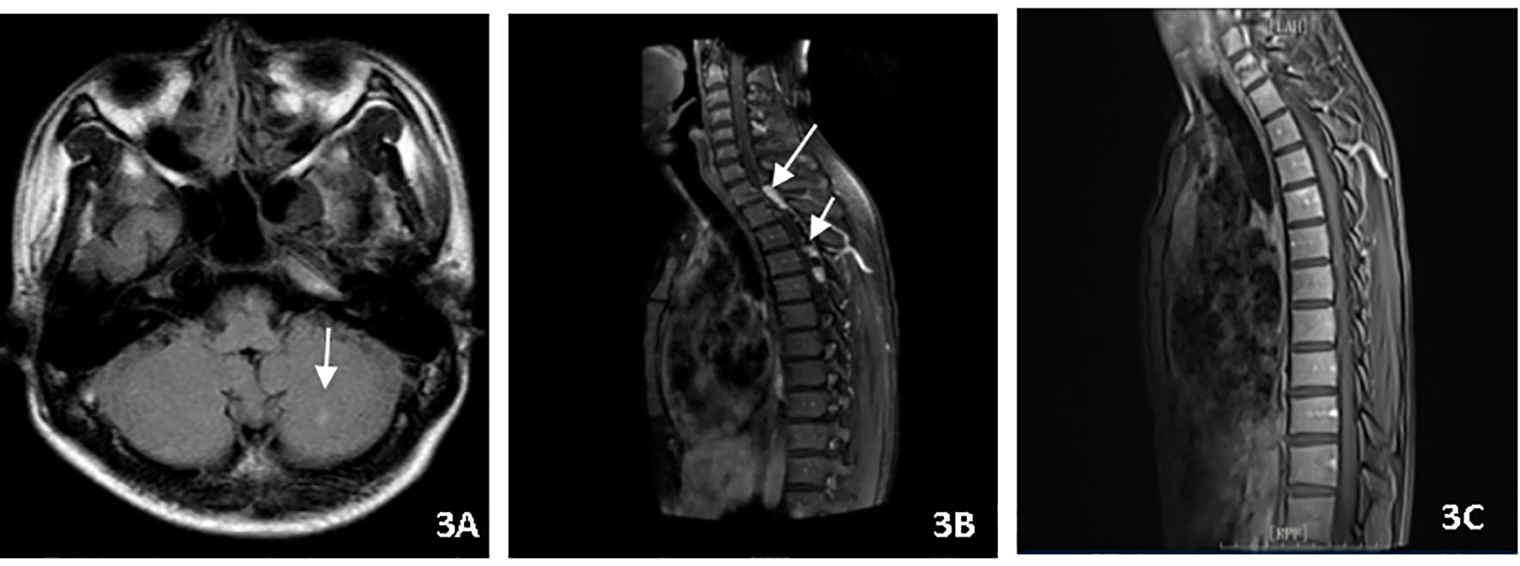

A 22-year-old male presented with fever, headache, vomiting, and coma. Clinical examination revealed meningitis and lethargy (GCS 12/15). MRI (Figure 3A) showed multiple enhancing nodular lesions from the left cerebellar hemisphere and the right occipital lobe to the right frontal lobe. CSF was positive for X-pert MTB/RIF assay with no RR. The patient was started on standard ATT and dexamethasone. The patient improved quickly and returned to normal consciousness a week later. The dexamethasone dosage was reduced gradually. Two months later, the patient complained of backache. A repeat MRI (Figure 3B) showed cervical and thoracic spinal membrane thickening and enhancement with multiple rounded lesions. Oral glucocorticoids (prednisone) were administered at a dosage 10 mg/d. The extent of spinal cord swelling and risk of cord compression was felt to justify the simultaneous initiation of thalidomide in an attempt to maximally inhibit inflammation. Therefore, thalidomide (3 mg/kg/day) was administered for 4 months, while the TB regime was continued for an additional 12 months. The patient remains clinically well (Figure 3C).

Figure 3

(A) Brain MRI showed multiple enhancing nodular lesions in the left cerebellar hemisphere. (B) Spin MRI showed cervical and thoracic spinal membrane thickening and enhancement with multiple rounded lesions. (C) Spin MRI showed the thickening and enhancement of cervical and thoracic spinal membranes were significantly improved.